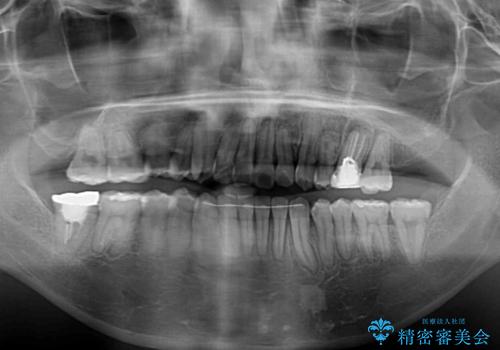

- 咬み合わない前歯と八重歯などのデコボコを気にして来院された患者様です。

上下前歯の位置を比較すると上顎が前方にあり、デコボコ改善でより上顎が前方に行く可能性があります。

開咬の改善にはインビザラインが有効であり、インビザライン単体での治療を検討しましたが、上顎前突を回避するために上顎左側第一小臼歯抜歯を行うこととしたため、補助装置とワイヤー矯正を併用した上で、インビザラインによる矯正治療を行うこととしました。

インビザライン矯正治療では、臼歯の圧下による前歯部の早期接触が大きな問題となっています。開咬では、その臼歯圧下を逆手にとって前歯部の非接触を改善させることができます。